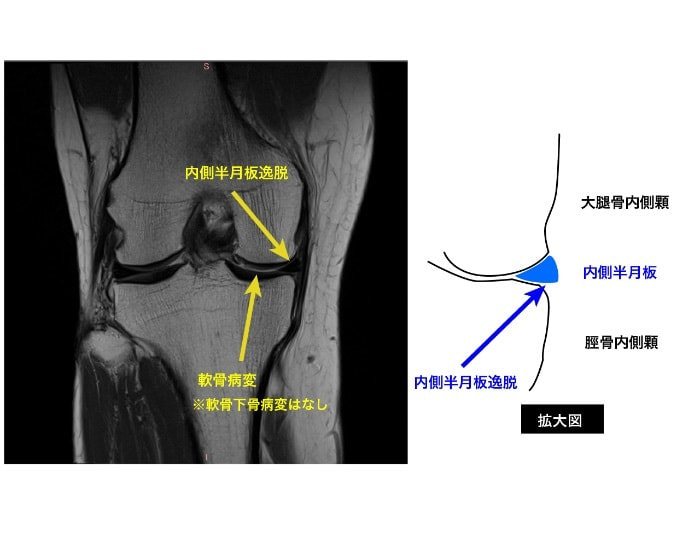

半月板には膝関節へ掛かる荷重ストレスを分散させるhoop機能というものがあります。

この機能が半月板損傷や逸脱によって破綻してしまうと、変形性膝関節症に発展していきます(急激な変形の進行の一因としてもhoop機能の破綻が関与していると言われています)。

その為、下のような画像が検査で判明したら、今のうちに出来る対応をしていく必要があります(MRIを提供してくれた患者様は、酷い変性は見当たらず経過観察となっていました)。

・荷重が偏らないように膝の使い方の再教育

・筋肉による膝関節の補強

・股関節や足関節といった関連部位の改善

など、様々な方法で状態を悪化させないようにしていきますが、『同じ症状』=『同じ問題』ではなく、リハビリの順序も一人一人違うため、その方にあった選択をしていく事が重要です。